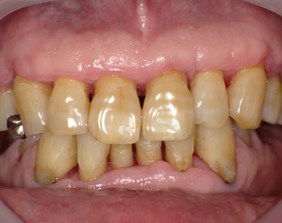

初期治療後

歯石取りをした後も歯周ポケットが4〜6ミリあります。降圧剤を内服しています。

手術中

歯茎を切開して根の周りに付いていた歯石(歯肉縁下歯石)を全部取りました。

外科手術後

歯周ポケットが2ミリに改善して歯茎がピンク色になりました。